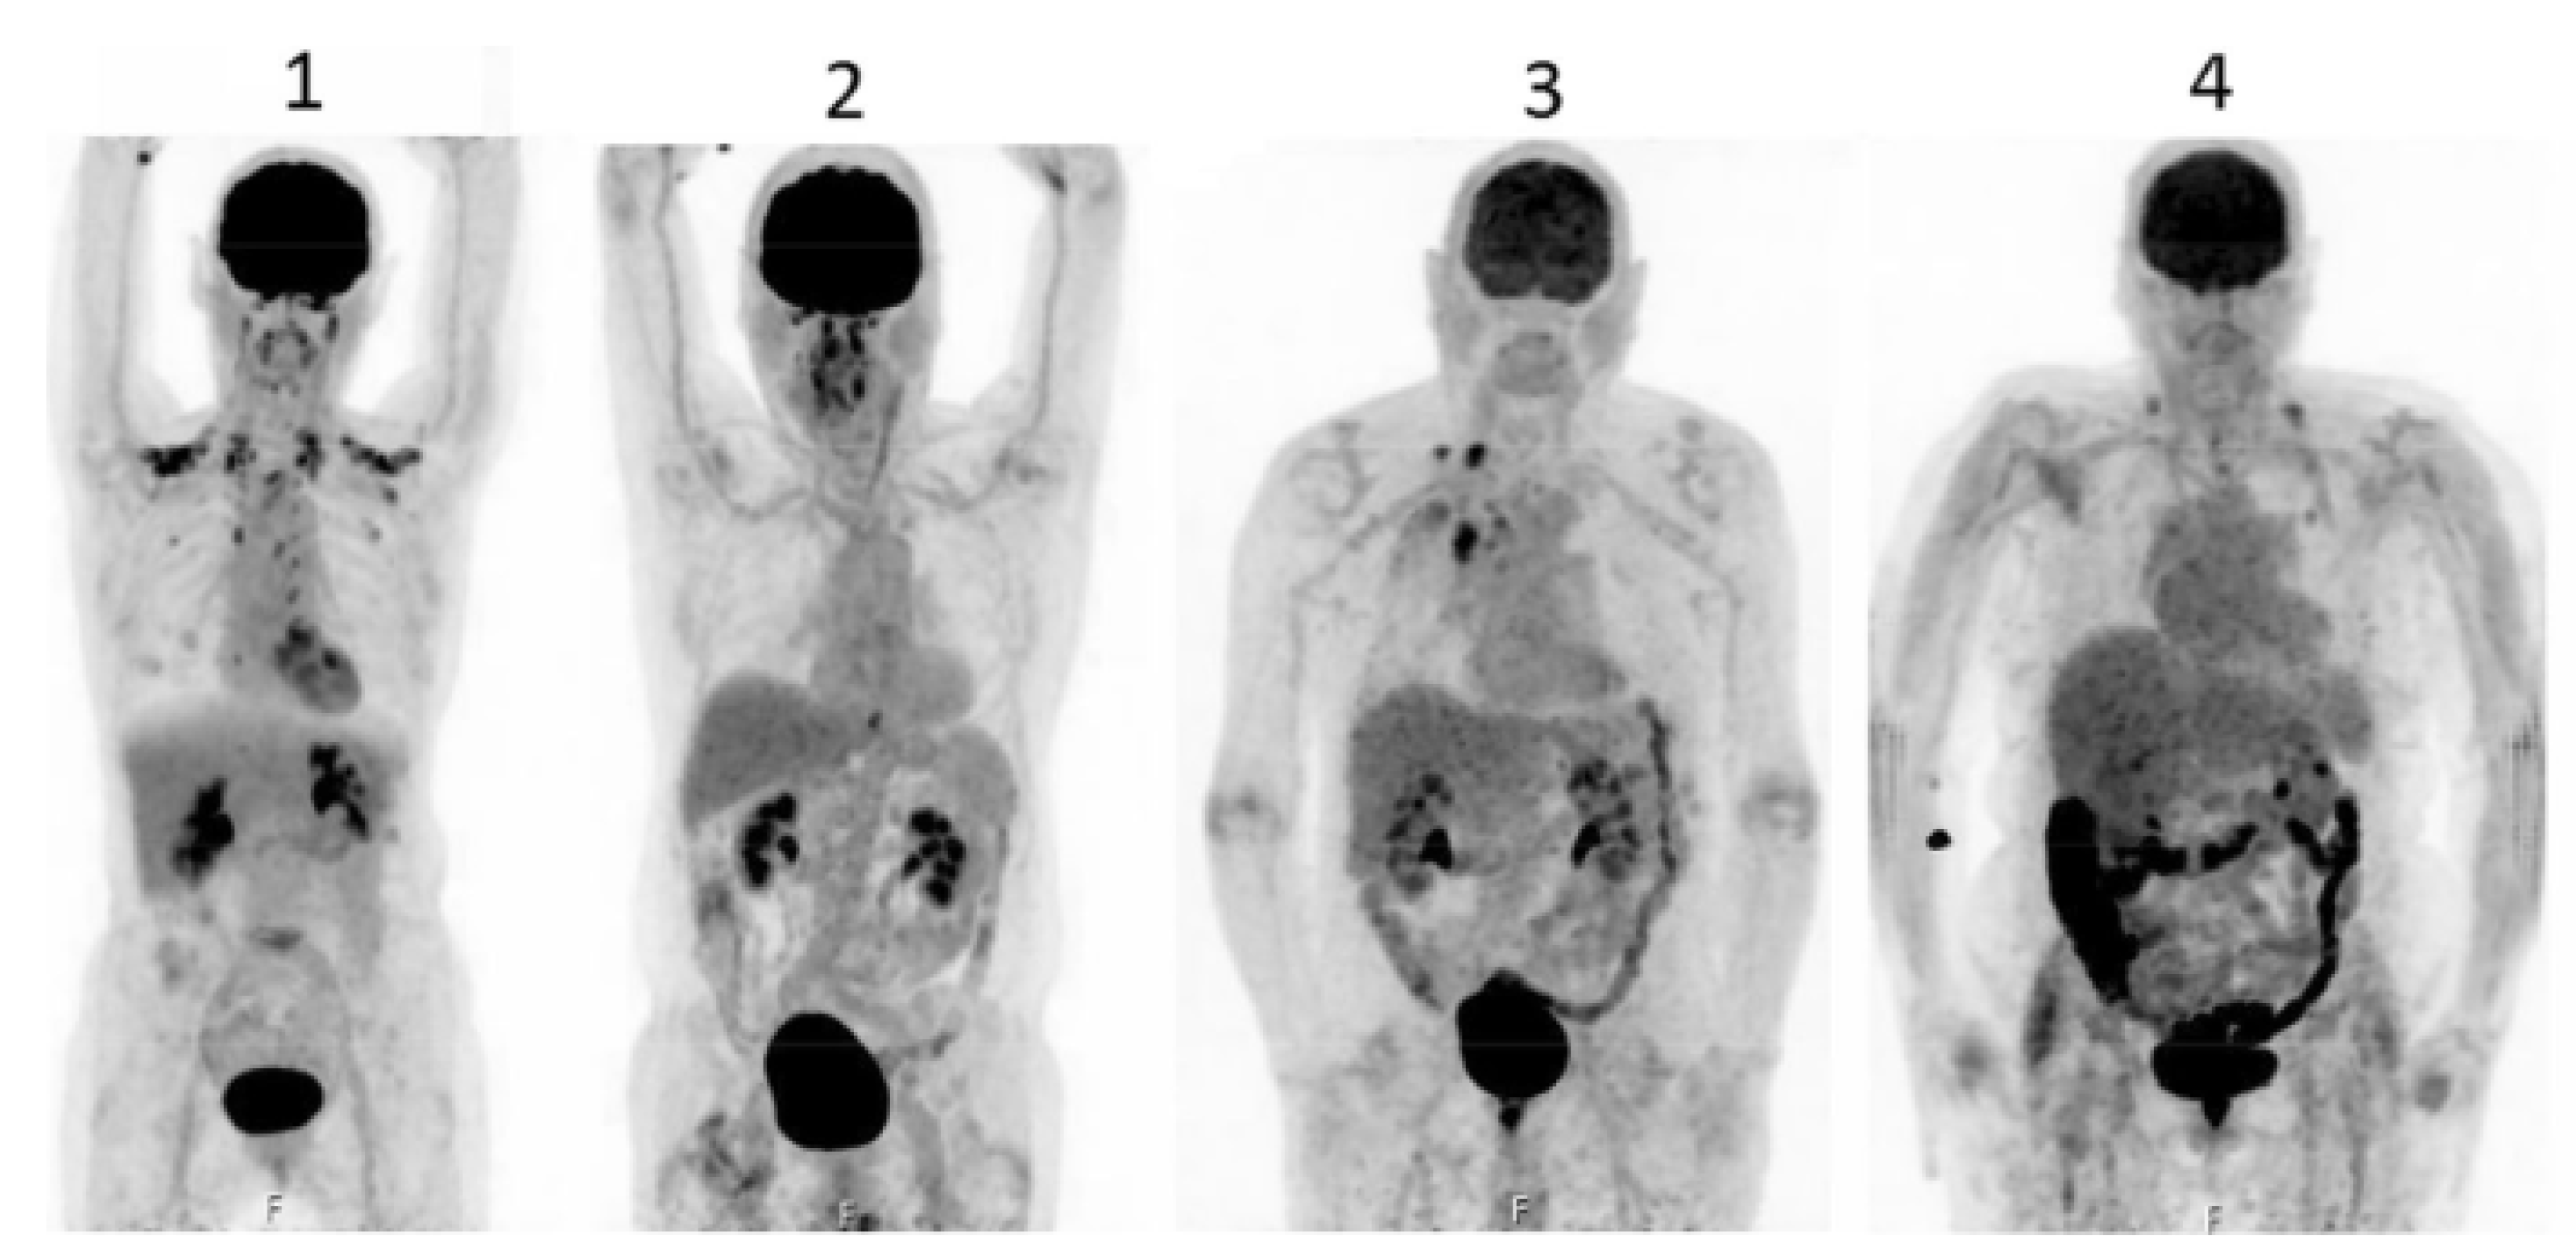

In a retrospective analysis, Kim and coworkers [169] described an accumulation of intravenously injected F18-FDG in the intestinal lumen of patients suffering from non-inflammatory diarrhea or constipation. Gontier and colleagues [170] retrospectively studied the localization of F18-FDG injected in type 2 diabetics and found a significant increase in the radioactively-labeled glucose in the wall but also in the lumen of the small bowel and the colon in patients treated with metformin compared to that of non-metformin-treated diabetics, which was not different from that of the non-diabetic controls [170]. The authors stated that “the digestive tract is the only tissue responsible for a large glucose utilization enhancement”.

Morita and coworkers [171], by using positron emission tomography (PET)-MRI, recently found that the maximum standardized uptake value (SUVmax) of F18-FDG in the intestine (jejunum, ileum, and right or left hemicolon) of metformin-treated diabetics was higher than that of the control group. More importantly, the study permitted to differentiate the SUVmax of the intestinal wall from that of the intestinal lumen. The SUVmax of the intraluminal space in metformin-treated diabetics was greater than that of the controls (Figure 2). On the contrary, the SUVmax of the intestinal wall was similar in both groups [171]. A temporarily increased accumulation of the injected tracer seems to be observed (Figure 3) also in the liver of metformin-treated diabetics up to 48 h after interruption of the oral uptake of the drug [171,172,173], suggesting a persisting uptake of the radioactive glucose mediated by circulating insulin as consequence of the “metabolic starvation”(?) induced by the biguanide.

Accumulation of F18-FDG in the large intestine (Figure 4) has been found also in persons who regularly use laxatives [175,176]. SUVmax can even reach levels that simulate those of colorectal neoplasms (Figure 5) in patients with chronic constipation [177].